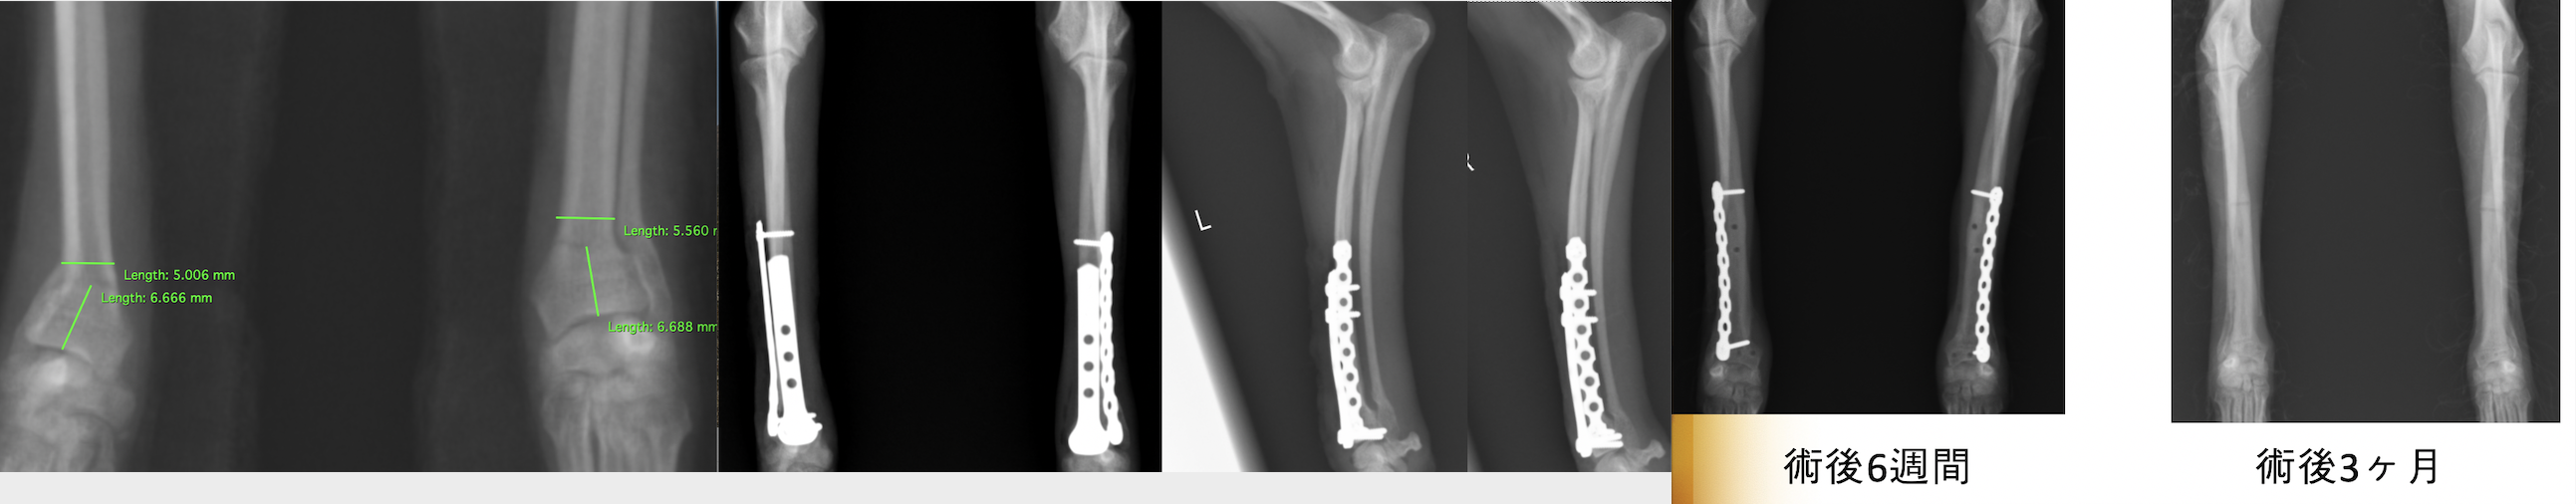

次の症例は11ヶ月のトイプードルで、スリングから飛び降りた後から足をケンケンするということで来院しました。左橈尺骨遠位斜骨折で、2日後に手術を実施しました。遠位骨折の場合尺骨(細い方の骨)には治療を行いませんが、骨折線も綺麗にあっているのがわかります。術後は次の日から足を着くことが可能で、1週間後に帰る時には通常に近い歩様で帰っていきました。その後1週間で抜糸となりますが、そこまでは散歩を5〜10分ほどにしてもらいます。ジャンプや激しい運動はしないでもらっています。その後2週間は散歩を15〜20分、その後1ヶ月は25〜30分で、その頃にプレートを1枚抜去します。

術後のレントゲン画像です。足もまっすぐになり、尺骨という骨も綺麗にあっているのがわかります。